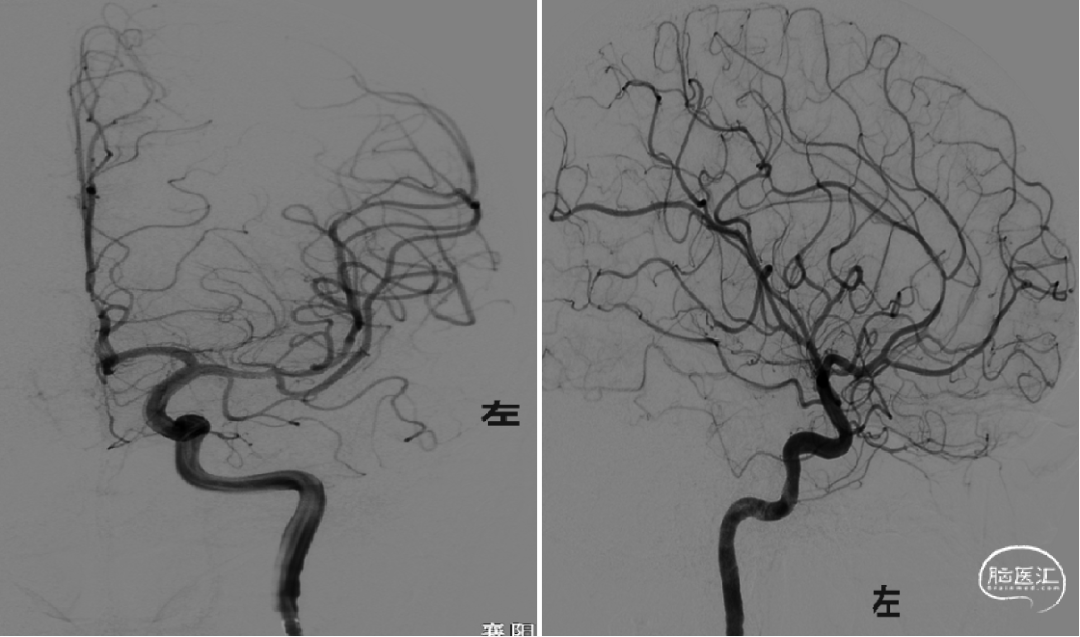

术前造影:

造影显示左侧大脑中动脉闭塞,右侧颈内动脉及后循环血管未见明显异常;左侧大脑前动脉通过软膜支部分代偿。

复查造影显示左侧大脑中动脉显影良好,M1段局部毛糙,前向血流:TICI分级:III级,予以替罗非班5ml动脉内缓慢推注,观察15分钟、30分钟分别造影,左侧大脑中动脉显影良好,考虑患者年轻,未放置支架。